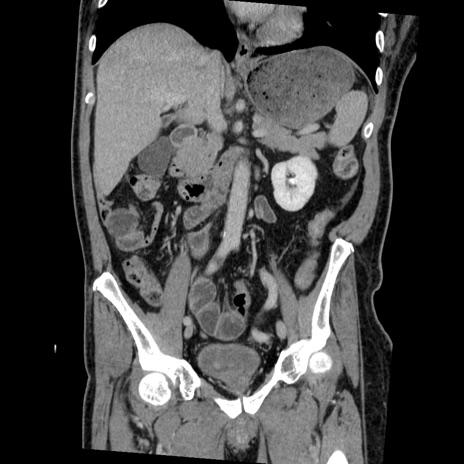

横断像

【症例】50歳代男性

【主訴】腹痛

【現病歴】AVMからの被殻出血のため回復期リハ病棟入院中。 本日午後3時頃急に下腹部痛が出現した。

【既往歴】AVM、被殻出血、虫垂炎、高血圧

【身体所見】意識晴明、左半身不全麻痺、会話の理解は良好、36.5°C、腹部:膨隆、全体に板状硬、下腹部正中に圧痛点あり、反跳痛-、筋性防御不明、右下腹部にope scar

【データ】WBC 9400、CRP 0.06